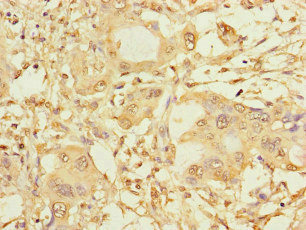

SPAG9 Antibody is a premium polyclonal that offers outstanding performance and reliability for demanding research applications. Rigorously validated for ELISA, IHC, IF, this antibody ensures consistent, reproducible results across multiple experimental platforms. Demonstrates excellent reactivity with Human samples, providing researchers with confidence in cross-species compatibility. Conveniently packaged in 50ug format to meet your experimental needs. For optimal performance, store at -20°C or -80°C and maintains stability for 12 months. Backed by rigorous quality control testing to ensure superior performance in your critical research applications.

ELISAIHCIF

IHC

1:20-1:200